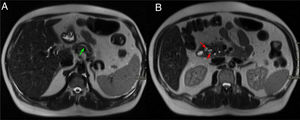

Varón de 74 años con ictericia y síndrome constitucional. Cortes axiales del abdomen con contraste intravenoso en fase arterial (A) y portal (B). Pequeña masa hipovascular en la cabeza - proceso uncinado del páncreas (flechas rojas, A) que envuelve a la arteria gastroduodenal y condiciona una dilatación de la vía biliar extrahepática e hidrops vesicular (flechas verdes, B).

Mismo caso que la figura anterior. Cortes axiales del abdomen en secuencia T1 con saturación grasa (A) y secuencias HASTE (B). Se observa en el aspecto anterior y medial del páncreas y en contacto con la 2.ª porción duodenal una masa hipointensa (flecha roja, A) identificada previamente en la tomografía computarizada con infiltración del surco pancreaticoduodenal (PD) (asterisco rojo, B). En la secuencia HASTE se observa hidrops vesicular, dilatación del CP (flecha verde en B) y ocupación del surco PD. El diagnóstico final fue de adenocarcinoma de páncreas.

El engrosamiento de la pared del duodeno con estenosis luminal secundaria y quistes en su pared o en el surco son hallazgos infrecuentes en el ACP, cuya presencia haría inclinarse hacia el diagnóstico de PS. Sin embargo, la existencia de una masa hipointensa en T1 con invasión vascular, adenopatías o infiltración del retroperitoneo haría más factible el diagnóstico de ACP (figs. 7 y 8)7,9,10. Otro hallazgo que diferencia el ACP de la PS es una dilatación, tanto del CPP como del colédoco (signo del doble conducto) (figs. 9 y 10)8. El patrón de realce de estas dos entidades en estudios poscontraste es también diferente y ayuda a diferenciar ambas entidades. El ACP presenta escaso realce y de forma homogénea, mientras que la PS suele realzar de forma tardía y heterogénea7.